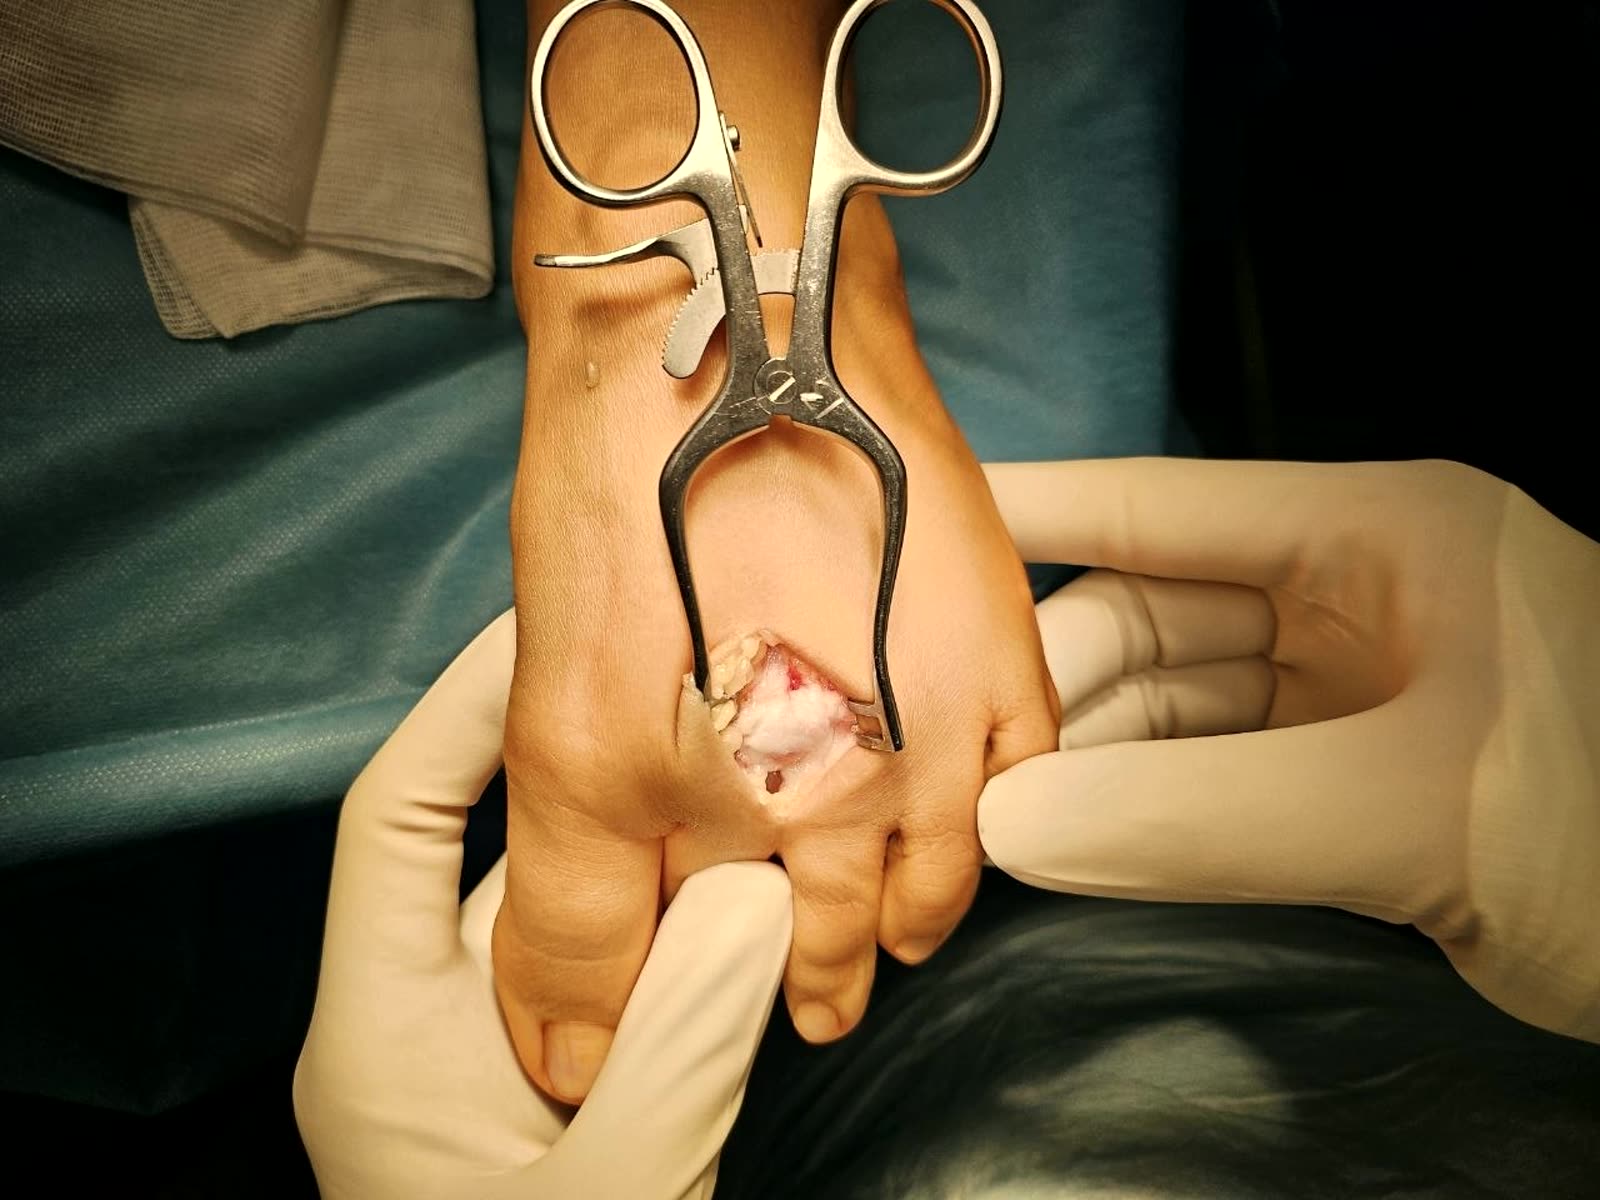

Рис. 13. Рефиксация остеохондрального фрагмента

Техника (артроскопическая):

- Диагностическая артроскопия через стандартные порталы (передне-медиальный рабочий, передне-латеральный обзорный)

- Идентификация и оценка ОХП пробником

- Дебридмент: удаление нестабильного хряща малой кюреткой. Стабильные края хряща сохраняются и формируются вертикально (perpendicular) для удержания кровяного сгустка

- Удаление склеротической субхондральной пластинки кюреткой

- Микрофрактуринг: перфорация субхондральной кости шилом (awl, обычно 60-65°) перпендикулярно поверхности. Отверстия на расстоянии 3-4 мм друг от друга. Глубина — до появления жировых капель (fat droplets), что подтверждает проникновение в костный мозг

- Снижение давления ирригации → визуализация кровотечения из перфорационных отверстий (подтверждение эффективности)

- Формирование стабильного кровяного сгустка (super clot)